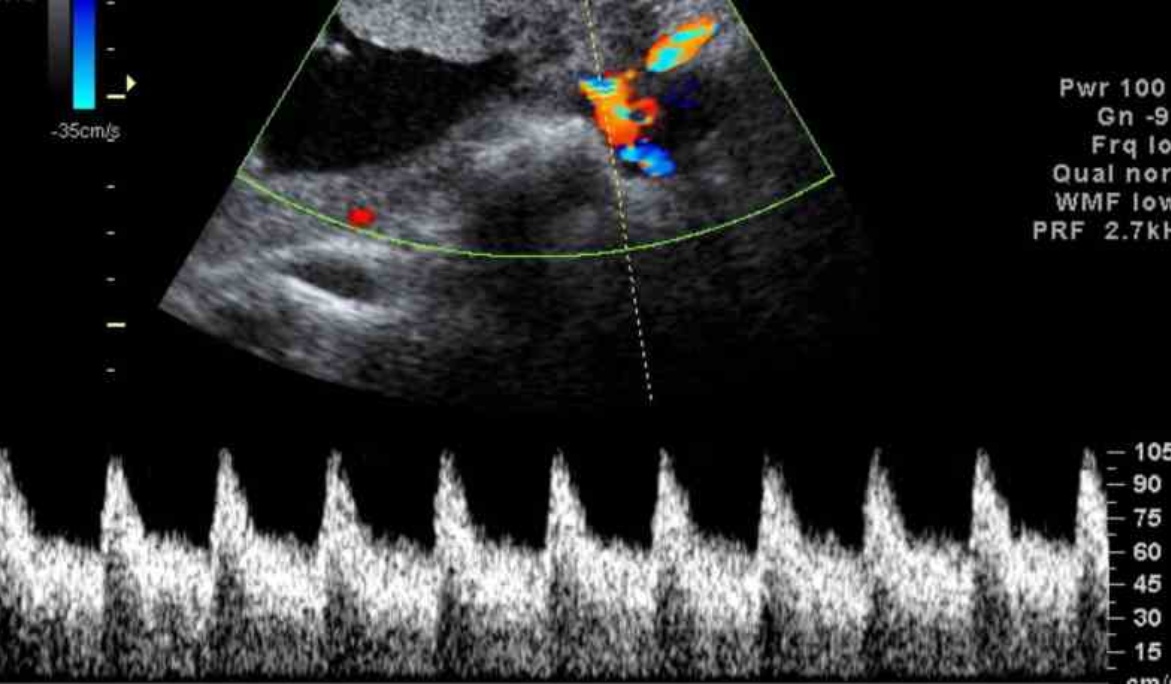

La ecocardiografía emplea ondas sonoras para producir una imagen del corazón y ver cómo funciona. Según el tipo de estudio ecocardiográfico que se realice, puede determinarse el tamaño, la forma y el movimiento del músculo cardíaco. Este estudio también puede mostrar cómo funcionan las válvulas cardíacas y cómo circula la sangre por el corazón. La ecocardiografía también puede suministrar información sobre las arterias. También se pueden detectar anomalías en la estructura del corazón, tales como defectos en las válvulas cardíacas, anomalías congénitas y aumento del grosor de las paredes o de las cavidades del corazón, como sucede en las personas con hipertensión arterial, insuficiencia cardíaca o deterioro de las paredes musculares del corazón.

La ecocardiografía puede emplearse para detectar un derrame pericárdico, en el cual hay acumulación de líquido entre las dos capas del corazón y la pericarditis constrictiva, en la que se forma tejido cicatricial a lo largo de todo el pericardio. Asì mismo detecta anomalías en el interior de las capas de la pared aórtica. La ecocardiografía es una de las técnicas más ampliamente utilizadas para el diagnóstico de las enfermedades cardíacas puesto que proporciona imágenes de una excelente calidad No invasiva, es inocua y relativamente accesible.